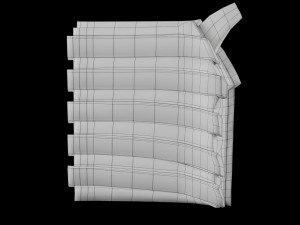

Breast anatomy histology detailed labelled precise to scale model 3D Модель

This is a 1:1 scaled model of right breast cut opened in sagittal plane to reveal its internal antomy and histology (schematic). The deeper parts and fascial layers are also depicted to give a very detailed approach to the model. The full layers starting from skin, nipple areola, till intercodtal muscles and ribs are also depicted.